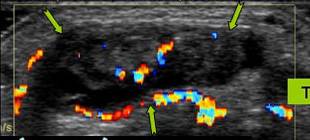

Hipertrofia n.median → cu hiperemie pe Doppler

Aspectul nervului pe IRM este normal